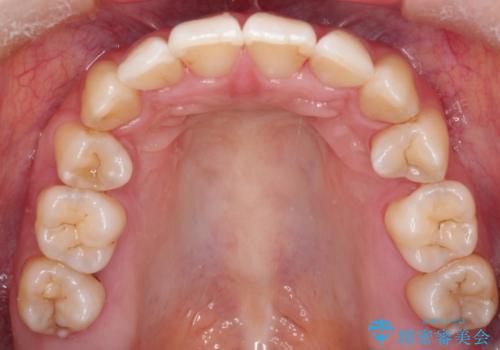

見た目、嚙み合わせ及び、治療期間や施術内容に大変ご満足いただきました。

- 前歯の見た目の改善を希望され来院された患者様です。

- 2年6ヶ月